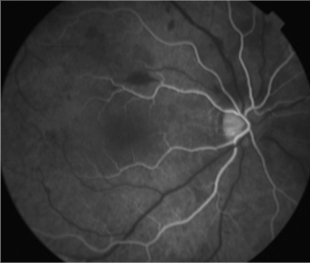

Angiografía OD

- Angiografía: teñido arterial, escape capilar, más tardíamente, no perfusion arteriolar y venular con teñido de las paredes vasculares y dilatación venosa.